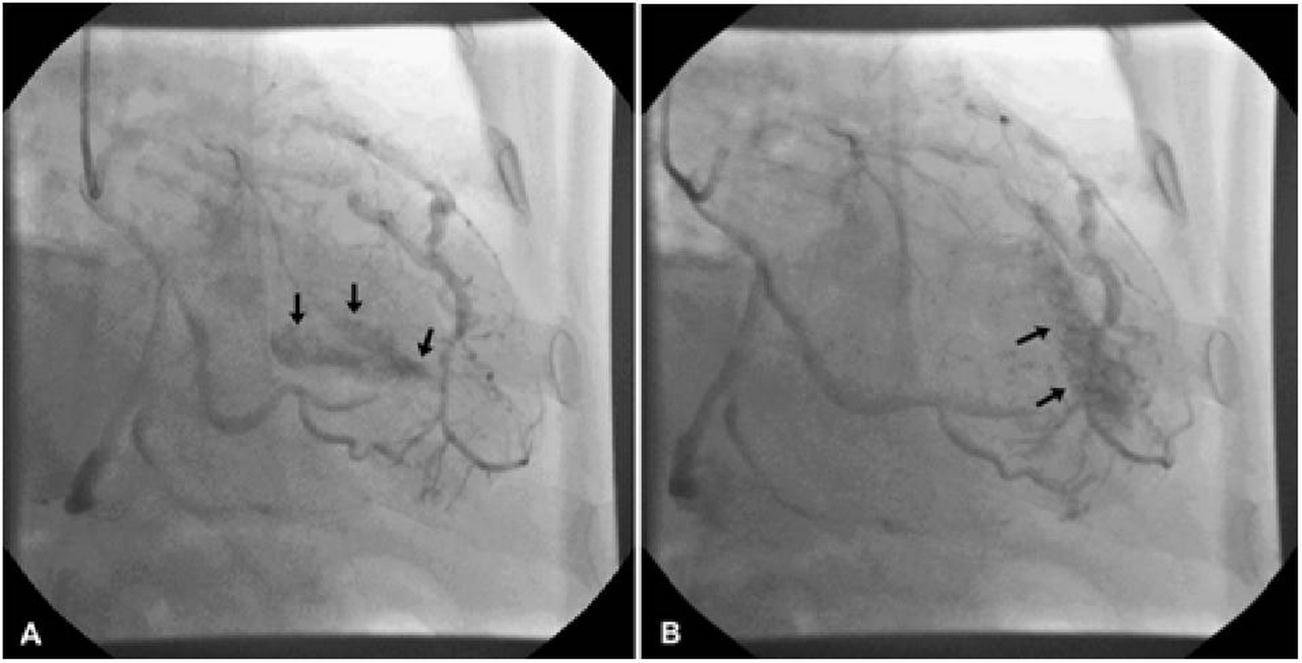

A 62 years old man six years ago underwent coronary angiography due to atypical chest pain. No coronary stenosis was observed while multiple coronary fistula coming from middle tract of left anterior descending (LAD) artery and draining to left ventricle cavity were detected (Figure 1). At discharged, he undertook antiaggregant therapy and no fistula’s closure indication was advised.

Figure 1.A/B. Left anterior descending artery fistula in left ventricular cavity: an angiography perspective.